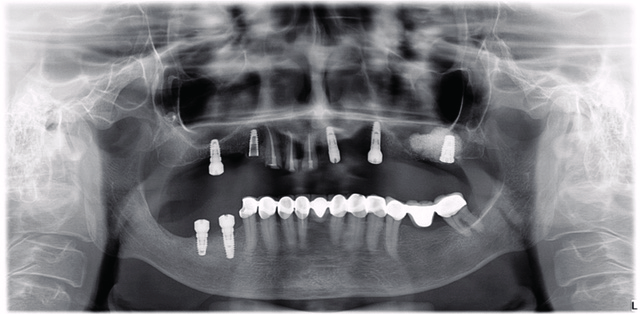

Lifting Oparation

Use of Biongraft Putty in sinus lifting operation.

Lifting

A- Before grafting procedure

B- 5 months after grafting procedure